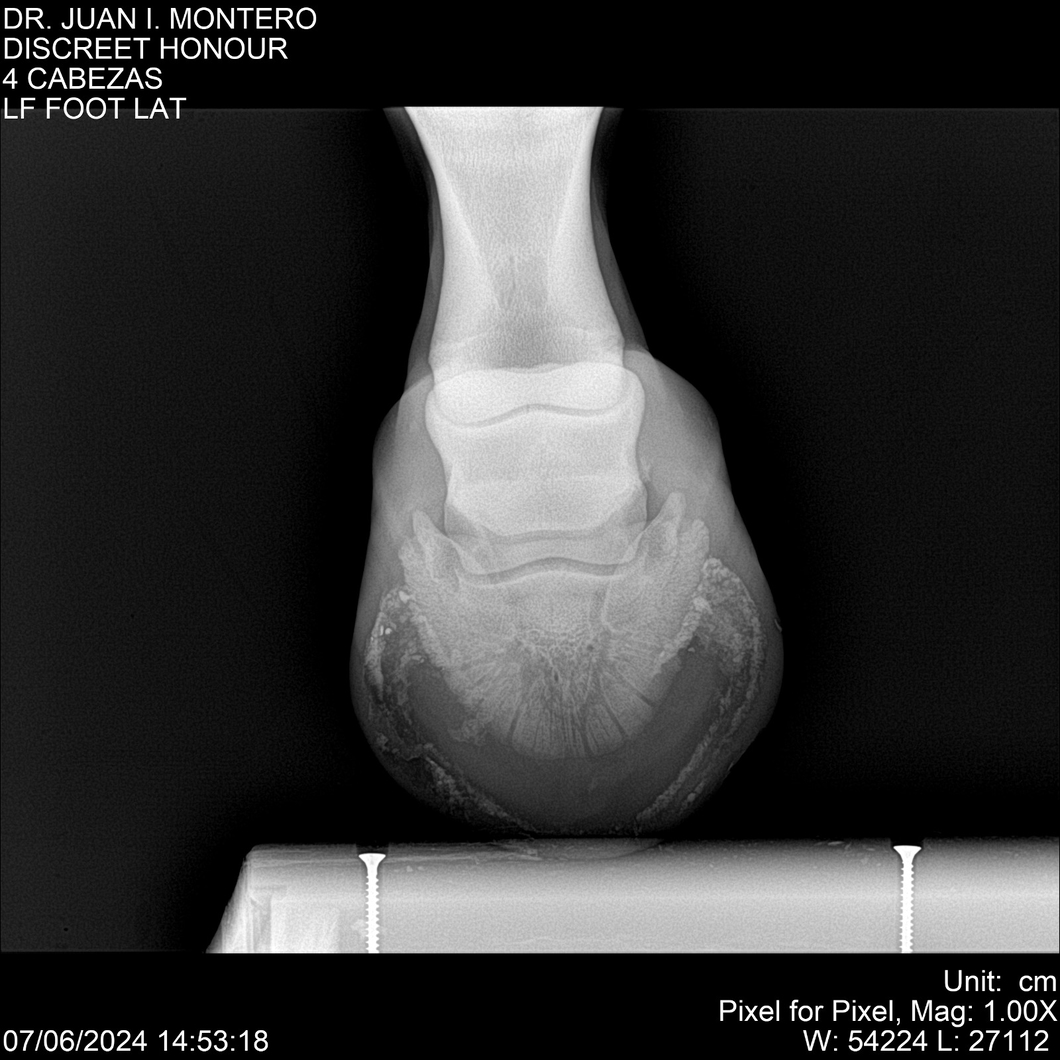

LOTE 6, DISCREET HONOUR 🔥 🔥 🔥 Lote Anterior Volver al remate Lote Siguiente Ficha Contacto Montevideo - Ficha del Lote Identificador: #281093 Categoría: Yeguarizos Montevideo - 82 Visualizaciones ClicData Contacto Empresa: Abelenda N. R., Walter Hugo Nombre*: Teléfono* : E-mail* : Mensaje Enviar Registrese gratis Este contenido Exclusivo está disponible sólo para usuarios registrados Ingresar